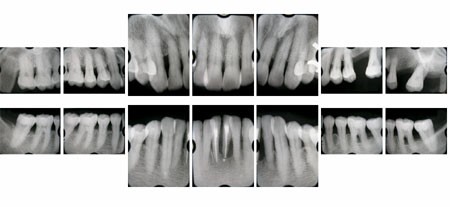

レントゲン1

1986年11月にこられた状態で、大臼歯部を支える骨が歯周病(歯槽膿漏)でずいぶんダメージを受けています。

レントゲン2

患者さんはその後まじめに歯ブラシをし(セルフケア)定期的に歯科医院のチェックを受け(プロフェッショナルケア) 2005年3月のレントゲン像です。ほとんどもたないと思った歯も1本も抜くことなく、現在ご自分の歯で快適に食事をしています。